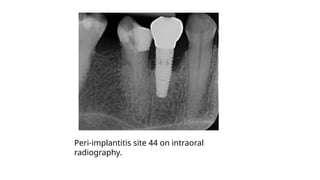

Peri-implantitis site 44 on intraoral

radiography.